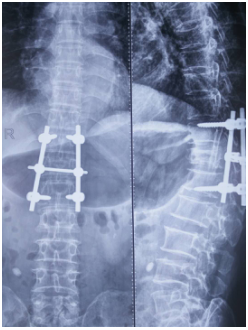

(上圖為患者術(shù)后X片)